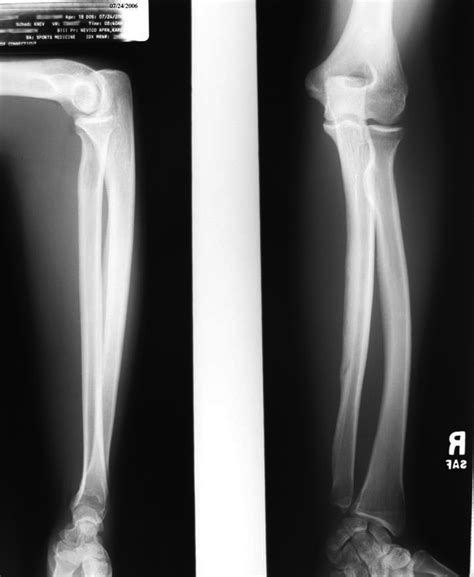

Diagnosing a hairline fracture wrist typically involves a combination of physical examination and imaging tests. The diagnostic process may include:

• Physical Examination: A healthcare provider will examine the wrist, checking for tenderness, swelling, and range of motion.

• X-Rays: X-rays are the primary imaging tool used to diagnose fractures. However, hairline fractures may not always be visible on initial X-rays.

• CT Scans: Computed tomography (CT) scans provide more detailed images of the bones and can help identify hairline fractures that are not visible on X-rays.

• MRI Scans: Magnetic resonance imaging (MRI) scans can show soft tissue injuries and are sometimes used to confirm the diagnosis of a hairline fracture.

In some cases, a bone scan may be recommended to detect stress fractures that are not visible on other imaging tests.